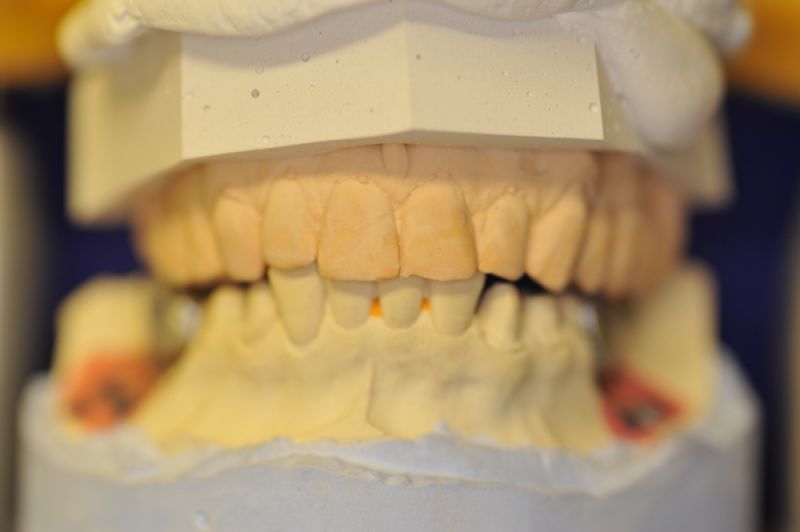

Neuromuskulär zentrierte Bisslage. Gerüste werden unbelastet durch das "Zahnfleisch" nach oben gehoben

Heute war nun Gerüsteinprobe, mit all den Problemen der Umsetzung zwischen Laborsituation und Mundsituation. Siehe Stichpunkt "Schnittstellenproblematik"! was bei Zähnen, auf Grund deren Eigenbeweglichkeit im Kieferkochen kein Problem wäre, ist bei drei unbeweglichen Implantaten ein Riesenproblem. Darüber spricht nur in aller Regel Niemand! Es musste viel fein nachgearbeitet werden.